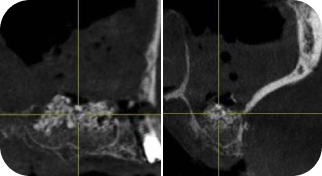

Get a detailed understanding of the technique of conducting an open and closed sinus lift, which will allow you to ensure stable results.

Direct or Indirect Sinus Lift. OPERATION TECHNIQUE

Learn how to work in complicated situations - perform a direct sinus lift surgery with 1 mm of residual bone.

RESIDUAL BONE IS 1 MM. WHAT TO DO?

Get an action plan for managing the membrane perforation, learn how to prevent inflammation and get to know the postsurgery prescriptions.

PERFORATION OF THE SCHEIDERIAN MEMBRANE